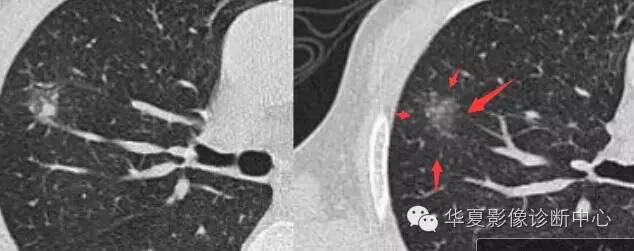

边界清楚,分叶征,空泡征

磨玻璃结节良恶性影像分析策略 都是支气管

磨玻璃结节良恶性影像分析策略

胸膜凹陷,分叶征